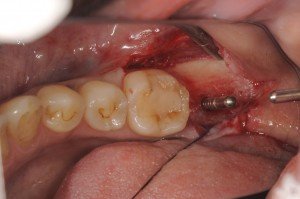

4.1mmのドリリングを終了して、インプラント体が埋入されたところです。

術後の状態です。

ヒーリングキャップが入って、1回法でのオペが完了したところです。